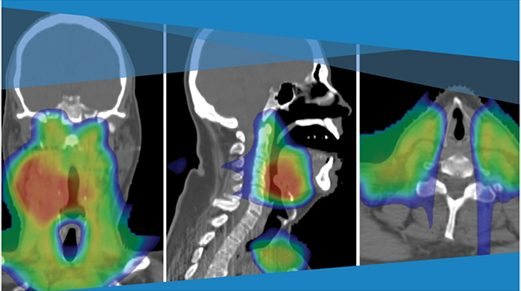

放射治疗计划示意图,展示辐射剂量对肿瘤的精确覆盖(来源:MD安德森癌症中心官网)